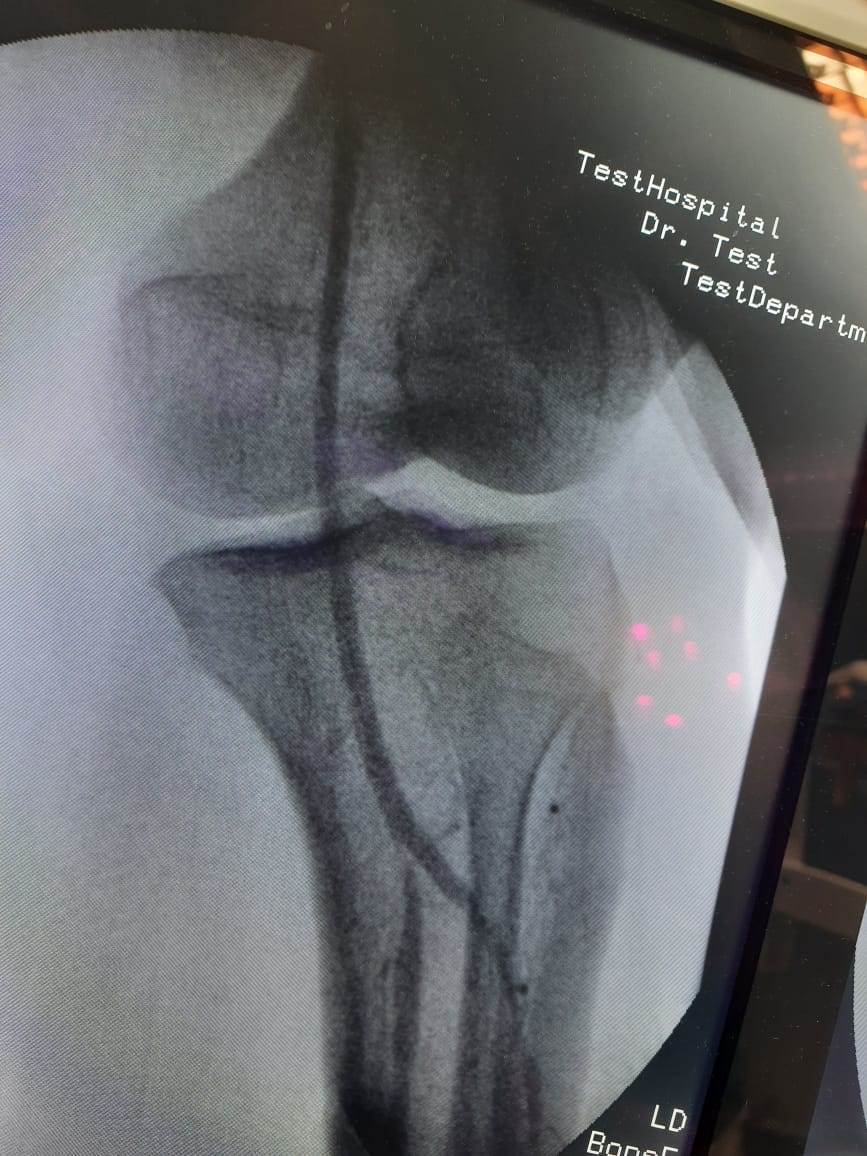

وأوضحت الهيئة برئاسة الدكتور أحمد السبكى رئيس مجلس الإدارة، أنه فور حضور المريضة محولة من وحدة صحة القرايا إلى مستشفى حورس التخصصي، بنظام الإحالة الطبية المعمول به في نظام التأمين الصحي الشامل الجديد، تم إجراء الفحوصات الطبية اللازمة لها، وتبين أنها تعاني من قصور حرج بالدورة الدموية بالطرف السفلي الأيسر وغرغرينا بالقدم نتيجة انسداد الشريان الفخذي والمأبضي الأيسر؛ وعليه تم عمل توسيع للشرايين باستخدام البالونات الموسعة واستعادة الدورة الدموية حتى القدم وإنقاذ ساق المريضة من البتر، وهي الآن بحالة صحية جيدة وحالتها مستقرة.